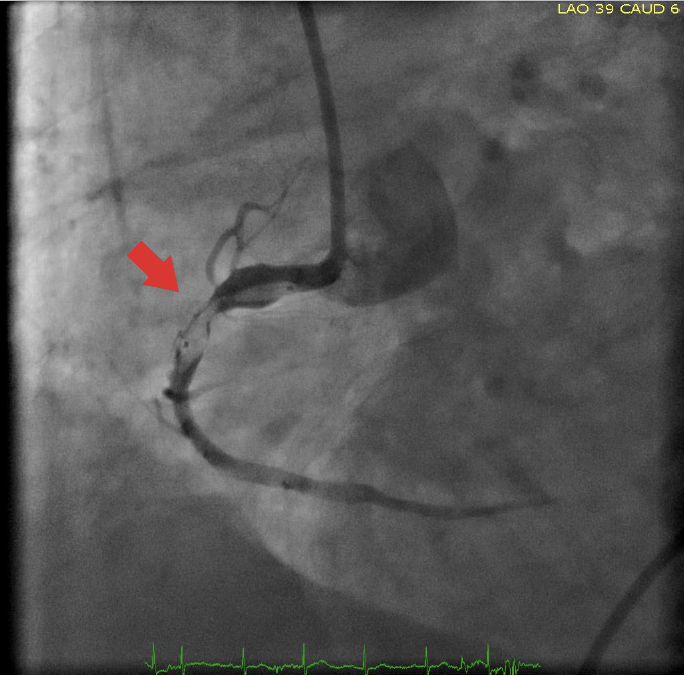

A 75-year-old man was referred to our clinic from another center following his complicated percutaneous coronary intervention (PCI) performed in the setting of an acute coronary syndrome. Angiographic images obtained during PCI demonstrated sequential implantation of 2 drug-eluting stents at the mid (3.0 x 28 mm) and proximal (4.5 x 19 mm) portions of the right coronary artery. However, the images also demonstrated a high-degree underexpansion of the proximal larger stent along with its jailed balloon. It was also reported by the performing interventionalist that he had attempted to pull back the balloon of the implanted proximal stent swiftly (before it was completely deflated) just following unplanned disengagement of the guiding catheter from the right coronary ostium. However, this maneuver resulted in abrupt balloon shaft fracture (outside the guiding catheter) leading to a freely swinging shaft appearance in the descending aorta (Figure 1 and Figure 2). Unfortunately, several attempts to retrieve the swinging fragment of the shaft failed. Moreover, intracoronary snare technique in an effort to grasp the distal portion of the shaft also failed. Finally, the shaft fragment was surgically removed (Figure 3) along with a bypass graft operation for the severely stenotic circumflex artery.